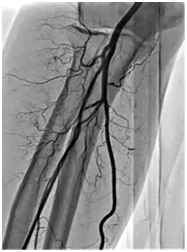

Regarding these factors, minimization of the risk of RAO can be achieved by adoption of several strategies. Some of these strategies include use of parenteral anticoagulation (UFH – 5000 IU preferred over 3000 IU, LMWH or bivalirudin), low profile arterial sheaths (5 or 6 F) or sheathless catheters and supporting the concept of patent hemostasis.1,2,4 The concept of patent hemostasis means to perform adequate hemostasis that simultaneously maintains and promotes antegrade flow in radial artery. It is believed that this technique is of major clinical importance and current data showed that patent hemostasis significantly lower the rate of RAO.2,8 Some authors suggest that concomitant use of the medication Trimetazidine post procedurally (after performed coronary angiography) may potentially inhibit neointimal hyperplasia and prevent RAO.2 Another practical tip is performing angiography of the right (or left) forearm (˗) as a routine procedure1 immediately before coronary angiography. The main concept here is to minimize radial artery wall injury, thus minimizing the risk for radial artery thrombosis and RAO. Routine angiography of the forearm gives us all necessary data concerning radial artery anatomy and variations as well as possible difficulties traversing it (loops, tortuosity, high take-off, radial artery spasm etc). In such cases operator can directly visualize radial artery impediments, anticipate possible.

According to the Consensus document on the radical approach in PCI (position paper by the EAPCI and Working Groups on Acute Cardiac Care and Thrombosis of the ESC) published in 2013, TRA offers lower access-site bleeding rates, particularly in high-risk patients for thrombotic or hemorrhagic complications. According to current recommendations, total reduction of both access and non-access-site bleeding rates is expected when TRA is associated with optimized anticoagulation.1 Nevertheless, a default TRA is safe and feasible in routine practice after appropriate training (starting from diagnostic coronary angiography, going through simple PCI in elective patients, next through PCI in NSTE-ACS patients, coming to PPCI in STEMI patients), but proficiency in TFA (Figure 1) is required because it may be needed as a bailout strategy, thus better results with TRA are expected with increasing procedural volume of operators, says this document.

Figure 1 Angiogaram of the right forearm problems, minimize radial artery injury and find appropriate solution to surpass it.